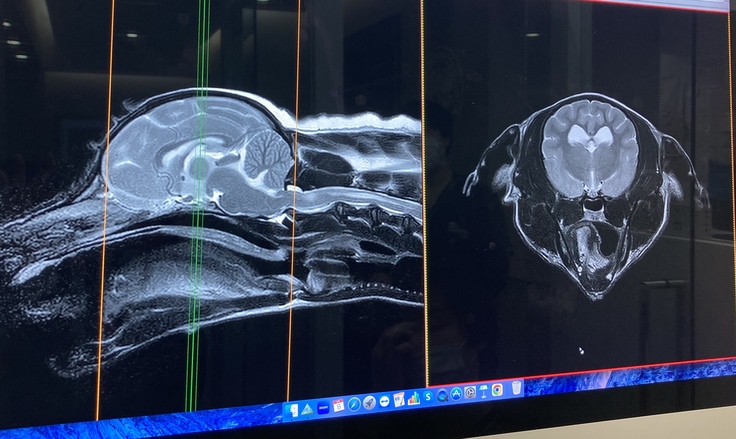

今年に入ってからは痙攣が始まり3月に地元の動物病院にてMRI検査を受けました。診断は、脊髄空洞症で、痙攣はその痛みからくる症状と言われました。

しかし、今年4月東京へ渡航し、動物医療センター(循環器科・脳神経科)での専門的な検査(CT・MRI)を2日間に渡り行った結果、MRI検査では「脊髄空洞症」と「てんかん」両方あること、その他にも多発性ヘルニア(腰椎、頚椎、他)が発覚し、痙攣の方はてんかんによるものと診断を受けました。 胆泥症・てんかん・脊髄空洞症に関してはこれ以上悪くならないように定期的な検診や毎月の通院、一生涯毎日の薬剤投与となりました。